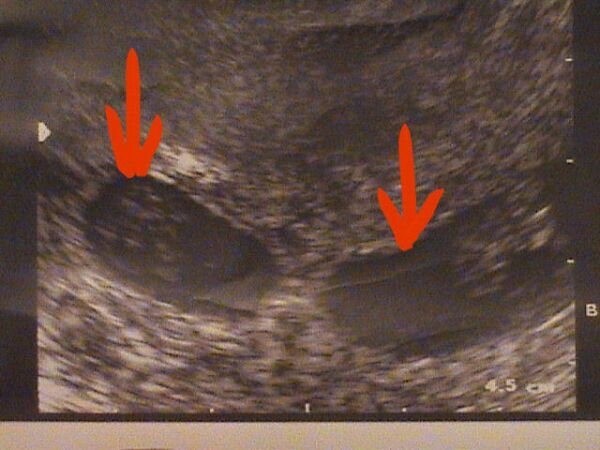

Ma voltunk UH-n, és KETTEN VANNAK!!!!!! Van egy nagyobb petezsák, 13 mm-es, benne már látható a kb. 3 mm-es testnyél, és van egy kisebb petezsák, 10 mm-es, de az is szép szabályos. Annyira boldog vagyok!!! Jövő héten még vissza kell mennem, a Konc dr látni szeretne, mielőtt szabadságra megy. És lecsökkentették a progeszteron injekciót is. Viki, ha jól emlékszem, Te is adodd, nem? Nálunk is János Kh. lesz, bár egyelőre addig még nem is merek előregondolni.